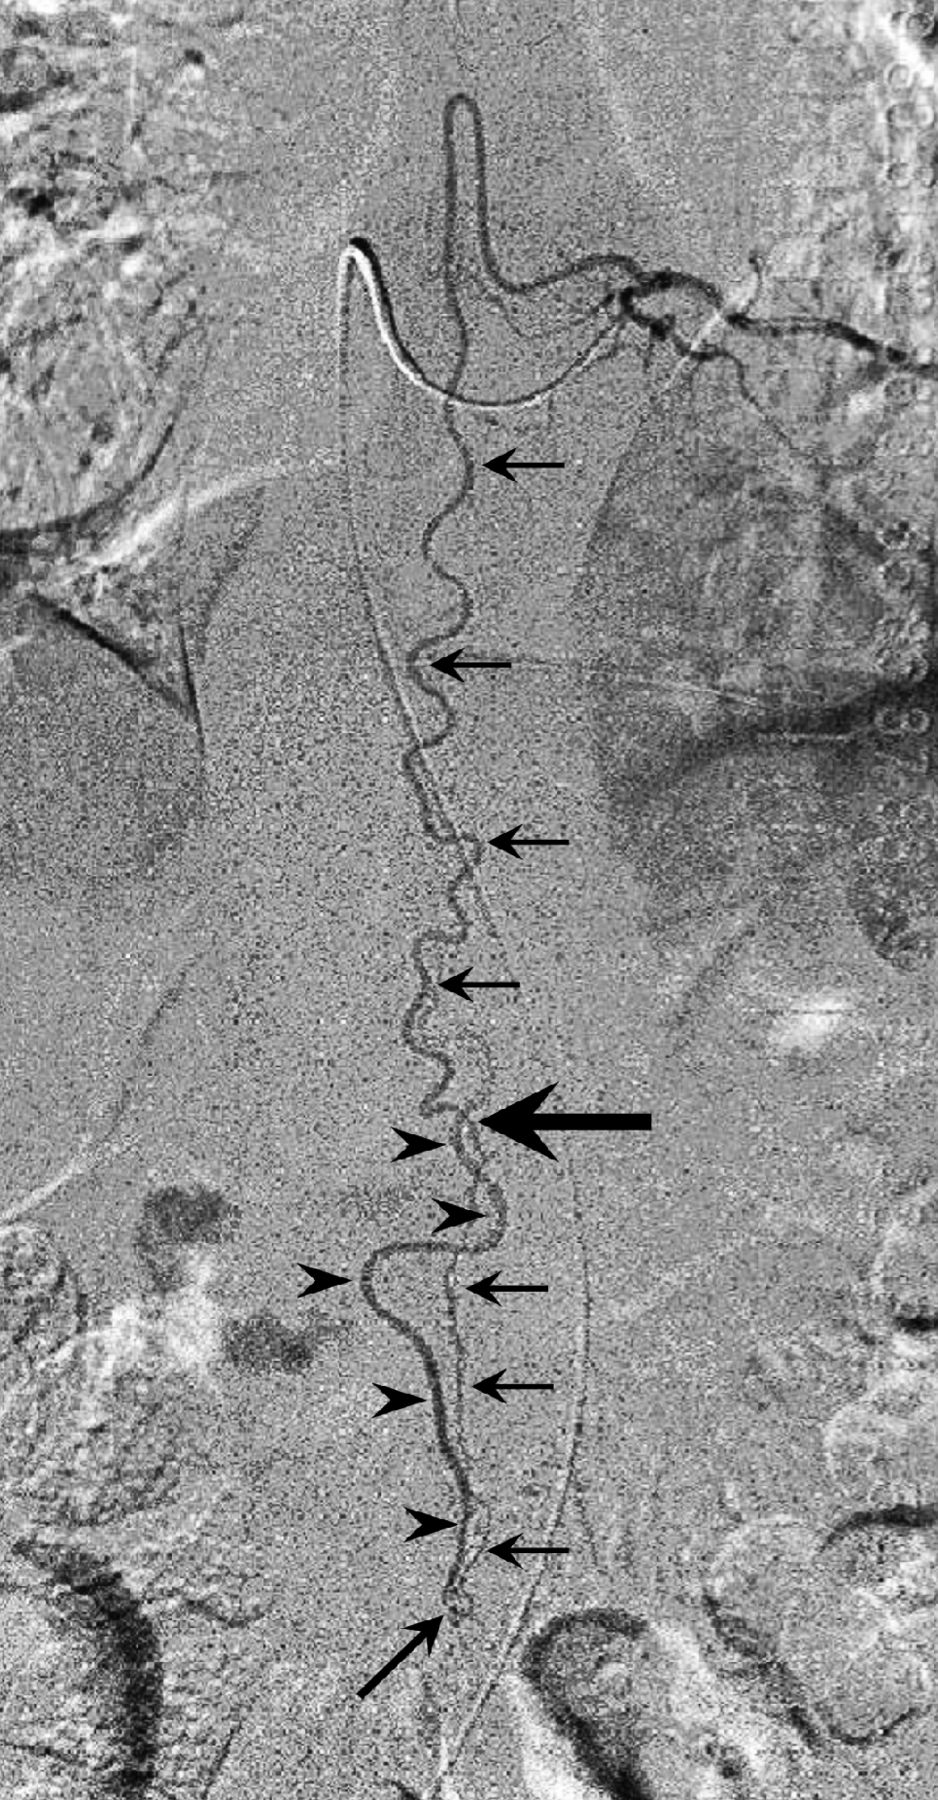

Left T9 intercostal artery angiogram in anteroposterior view shows the extension of the anterior spinal artery (arrows) traveling caudally to form an AVF at the L2 level (oblique arrow). The ascending draining vein shows a characteristic wavy pattern (arrowheads). Note the change in the course and caliber of the ASA at the conus medullaris apex (large arrow), suggesting a change of the feeding artery to a radicular artery. Reprinted with permission from Figure 2c in Tanioka S, Toma N, Sakaida H, et al. A case of AVF of the cauda equina fed by the proximal radicular artery: anatomical features and treatment precautions. Eur Spine J 2018;27(suppl 3):281–86.